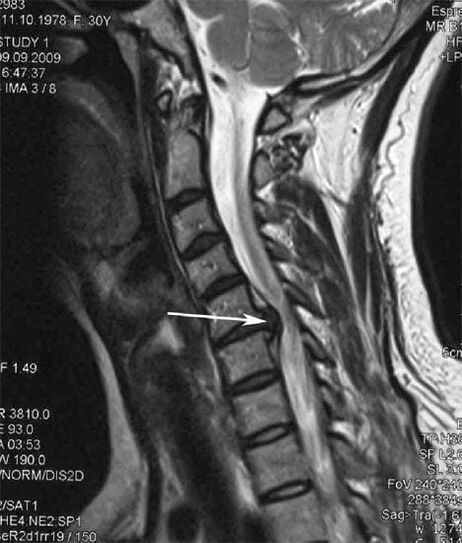

Nas fases iniciais, a osteocondrose detéctase mediante resonancia magnética. Máis tarde, a patoloxía pódese diagnosticar mediante radiografía. Nas radiografías da columna cervical, a diminución da distancia entre as vértebras, os cambios patolóxicos nas articulacións facetarias e a osteofitose fanse perceptibles.

Moitas persoas quéixanse de que non poden virar o pescozo debido á forte dor que aparece despois de levantar de súpeto algo pesado. Este fenómeno indica a formación dunha hernia discal. A causa da dor nas costas, no pescozo e no membro superior é o pinchazo dunha das raíces nerviosas que emerxen da medula espiñal.

| Osteocondrose cervical | A aparición de cambios patolóxicos nun ou máis segmentos de movemento da columna vertebral. Mobilidade da columna vertebral deteriorada, desenvolvemento de síndromes de dor miofascial e beliscar as raíces da columna vertebral | Dor, parestesia e alteracións motoras na rexión cervical, que se estenden á parte posterior da cabeza e aos membros superiores. Detección de cambios característicos na columna vertebral en resonancia magnética e radiografías (osteofitos, diminución da distancia entre as vértebras, signos de dano nas articulacións intervertebrais) |